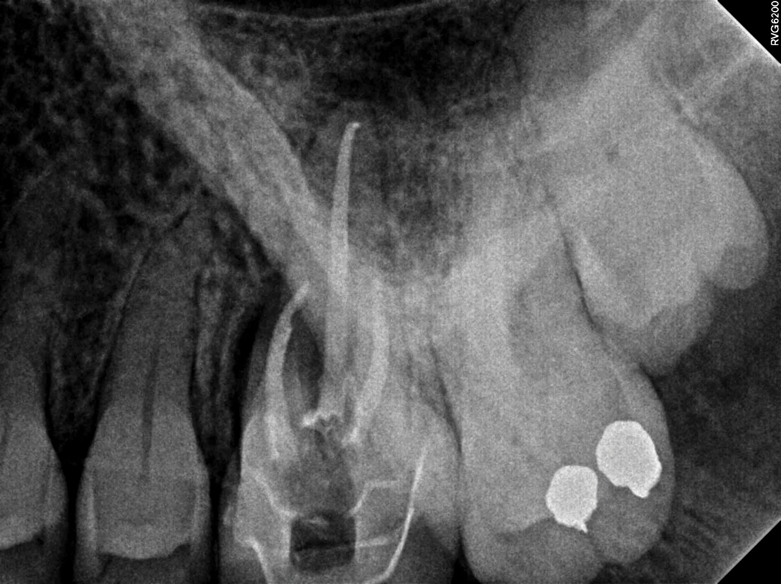

Fig 4. This penicillin-allergic patient presented with facial swelling secondary to pulpal necrosis with acute apical abscess on tooth No. 14 (Fig 2 and Fig 3). The swelling was consistent with cellulitis, thus systemic antibiotics were indicated in addition to definitive treatment by nonsurgical root canal therapy (Fig 4). Prior to 2019, clindamycin would have been the drug of choice, but newer guidelines warranted first-line use of cephalexin instead.10 Treatment in this case was initiated concurrently with antibiotic prescription and completed over two visits with the use of interappointment, intracanal calcium hydroxide. The infection resolved after treatment without complication.